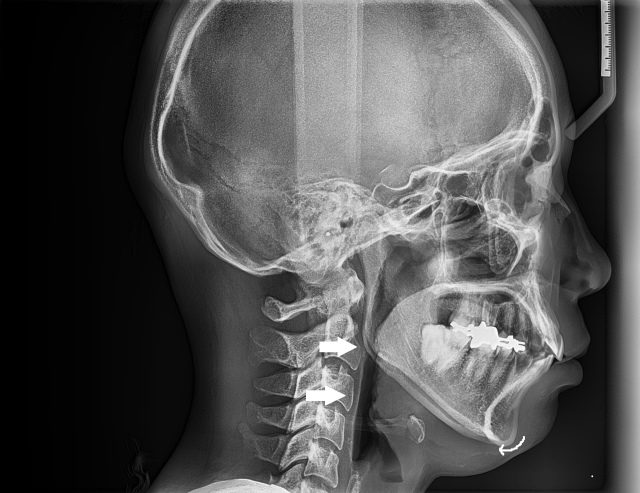

一番上の矢印は咽頭扁桃(アデノイド)が腫れている箇所を示している。下の矢印は口蓋扁桃の腫脹により舌が押されて特に気道が狭くなっている箇所 (10代前半女性)